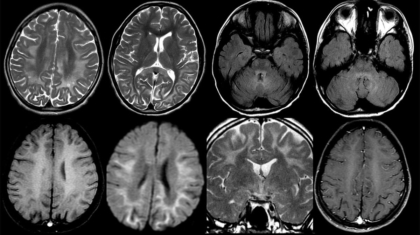

A 16-year-old male presented with short stature, bilateral ptosis, diplopia, and Type 1 diabetes mellitus. Family history is significant for short stature and ptosis.